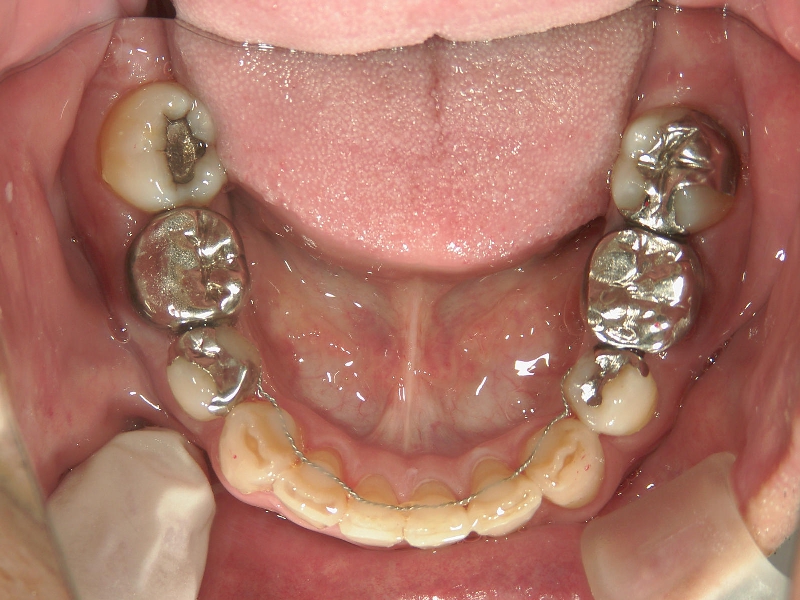

矯正_灰色.pngno.22_8175_治療前_下.jpg矯正_灰色.png

矯正歯科 治療後 左上6番欠損のため、7番を6番の位置へ前方牽引

矯正_灰色.pngno.22_8175_治療後_下.jpg矯正_灰色.png